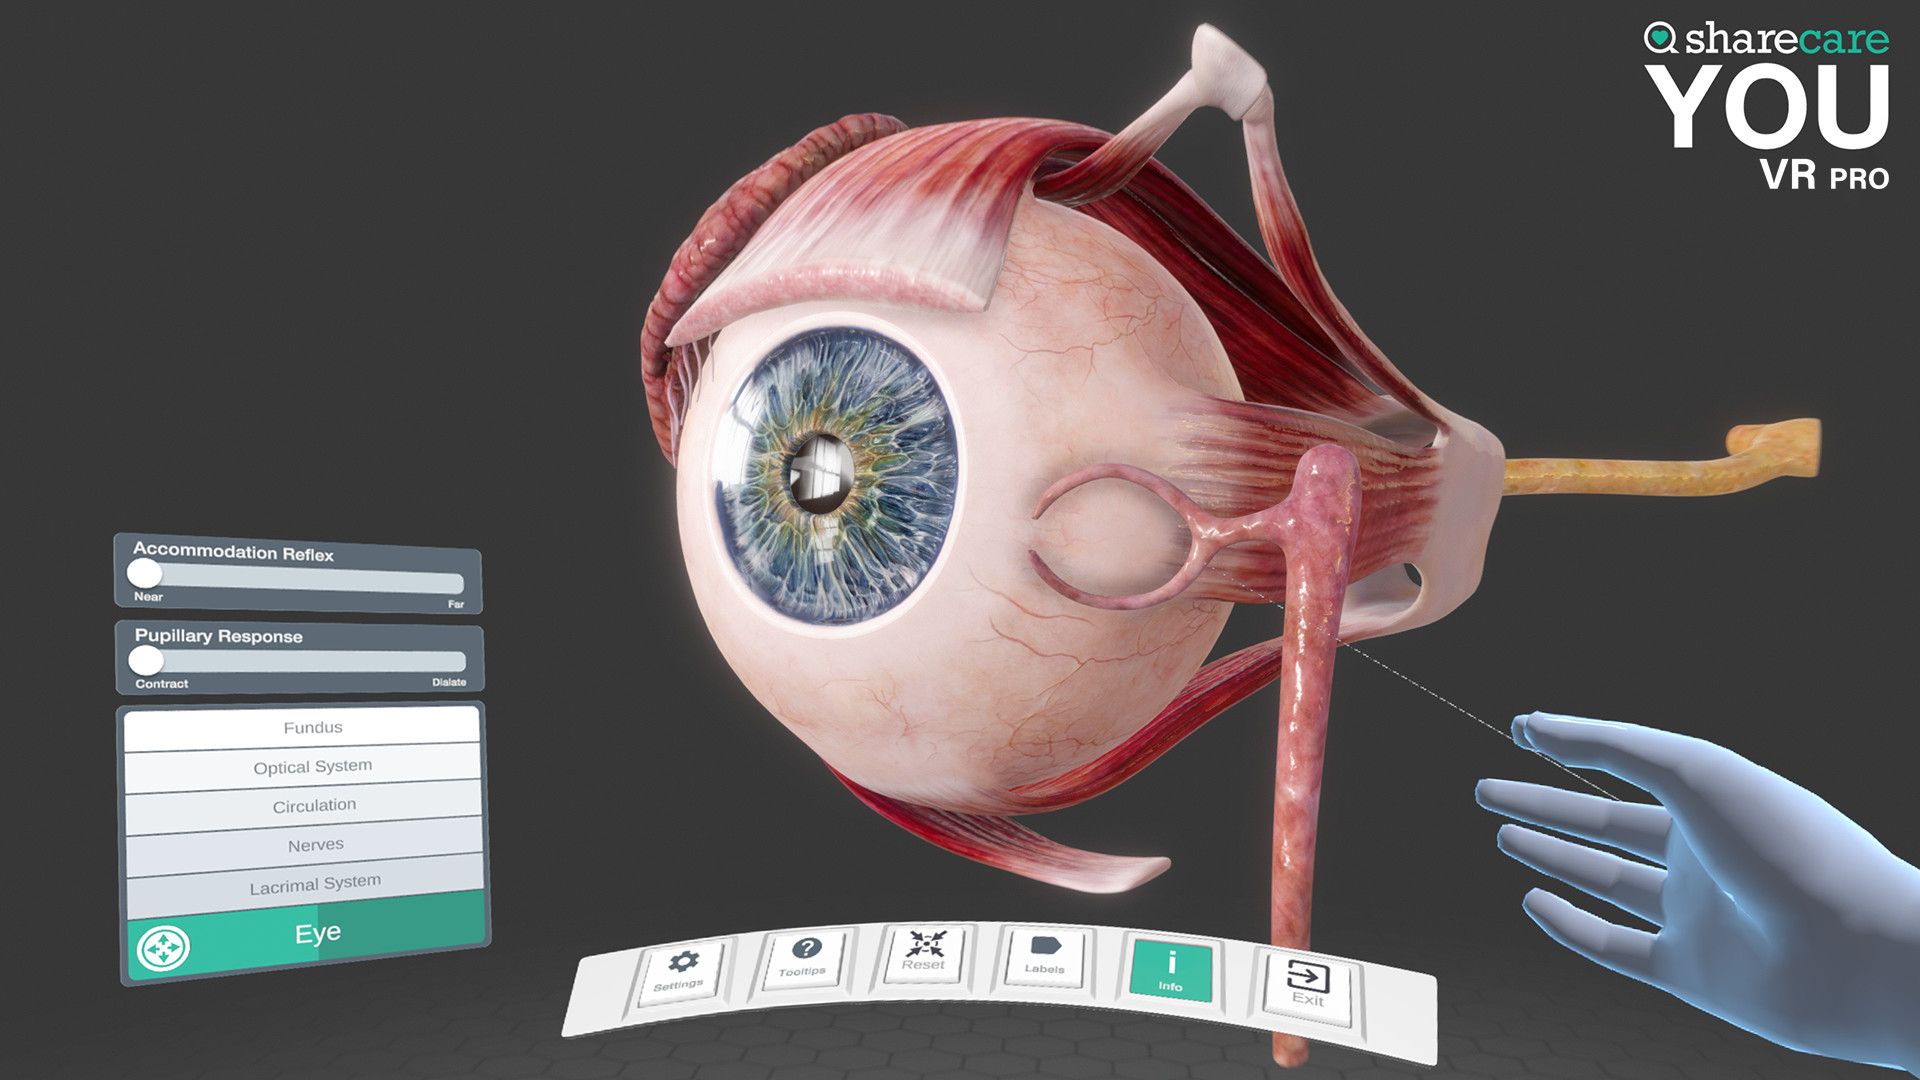

The winner of the 2019 Appy Best VR App is now available on Mac and PC, with more content, bolder graphics, and enhanced features! Sharecare YOU VR is a fully immersive, photorealistic simulation of the human body, enabling anyone to explore its astonishing details in full 360 degrees. Interested in learning about a specific organ? With the click of a button, travel inside, visualize its natural function, and dive deeper. Want to learn even more? Check out the many tags and labels along the way to gain even more information and insight. Easily customize YOU to better understand physiology and simulate disease. You can even personalize our avatars to be a virtual you – your health, your conditions. It really is all about YOU. With YOU VR PRO, users can create visually compelling, high-quality educational content. Build YOU lectures and presentations easily, with the help of video and voiceover recording, and the ability to draw and add your own text. You can also be the star within these videos using our web-cam feature.

- YOU content - an expanding library of over 40 different scenes to explore including anatomy, physiology, conditions, and treatments

- Informative labels and scene information

- Completely updated user interface with unique interactive controls

Looking to use the content for Business Purposes? Get the Sharecare YOU VR Pro version and have the ability to use all the amazing content for Business Purposes. Take advantage of breathtaking graphics and never seen before views of the human body. Your ability to better communicate human anatomy and physiology with your customers and/or students is at your fingertips!